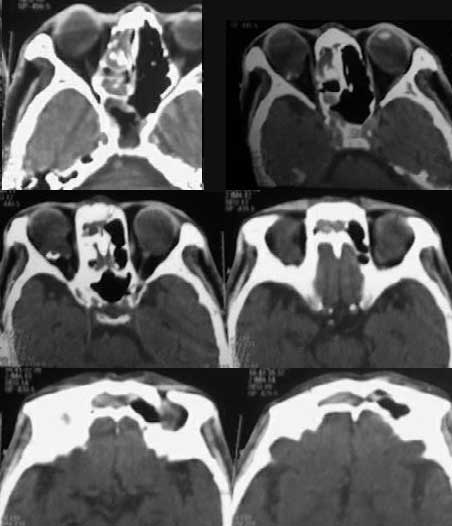

患者男性,78岁,一年前曾因右鼻窦息肉手术,病理中分化鳞状细胞ca。

下面是一年前的鼻窦ct片